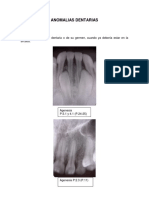

Dilaceracin

La dilaceracin es frecuente en

los dientes permanentes y el

diagnostico se hace a travs

del examen radiogrfico.

En esta imagen podemos

observar el 42 con una

dilaceracin a nivel del tercio

apical de la raz.

Tambin observamos un diente

supernumerario (mesiodens)

con una dilaceracin a nivel del

tercio cervical de la raz.